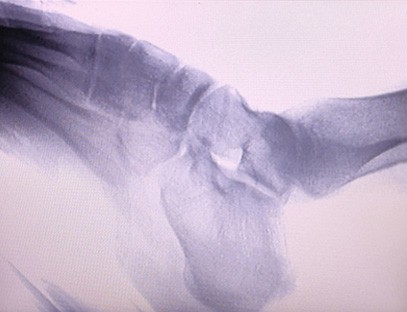

Una màquina de raigs X portàtilés un instrument portàtil de baixa dosi de radiació i molt segur que pot obtenir imatges d'alta qualitat alhora que redueix l'exposició a la radiació. Compensa les deficiències dels grans equips hospitalaris i es pot moure i transportar en qualsevol moment. Especialment indicat per a unitats i particulars amb pressupost insuficient i requeriments baixos d'imatges. La nostra màquina de raigs X de nova generació està equipada amb una pantalla gran d'alta definició de 10 polzades, que té un rang d'angle de visió més gran i pot veure completament a través de tota la palma, incloses fractures, luxacions, artritis i tumors ossis. Es pot connectar a una impressora de pel·lícules per imprimir pel·lícules ortopèdiques i també es pot utilitzar per a la producció i proves industrials. No cal una cambra fosca, perspectiva directa, observació en temps real. Aquesta màquina té un sistema d'imatge d'alta resolució que pot capturar imatges de qualsevol estructura òssia de manera molt clara. Proporcionar els millors equips i solucions de proves de raigs X per a fabricants de productes mèdics, mascotes, industrials, electrònics, departaments d'inspecció i manteniment i laboratoris d'investigació.

Especialització:Dissenyat per a les necessitats de les clíniques ortopèdiques, especialment indicat perImatge de raigs Xd'extremitats com mans, canells, colzes, espatlles, genolls, turmells, etc.

Imatge clara:La tecnologia d'imatge digital avançada s'utilitza per proporcionar imatges de raigs X d'alta qualitat, ajudant els metges a diagnosticar la malaltia amb precisió.